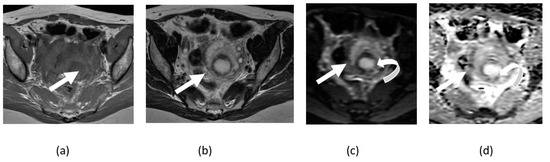

3.2. Adnexal Torsion